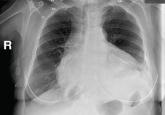

ArticleAn alerting sign: Enlarged cardiac silhouetteAuthor:Shemy Carrasso, MDPublish date: December 1, 2015Suspect pericardial effusion in patients with symptoms of impaired cardiac function and new symmetric cardiomegaly.Read More